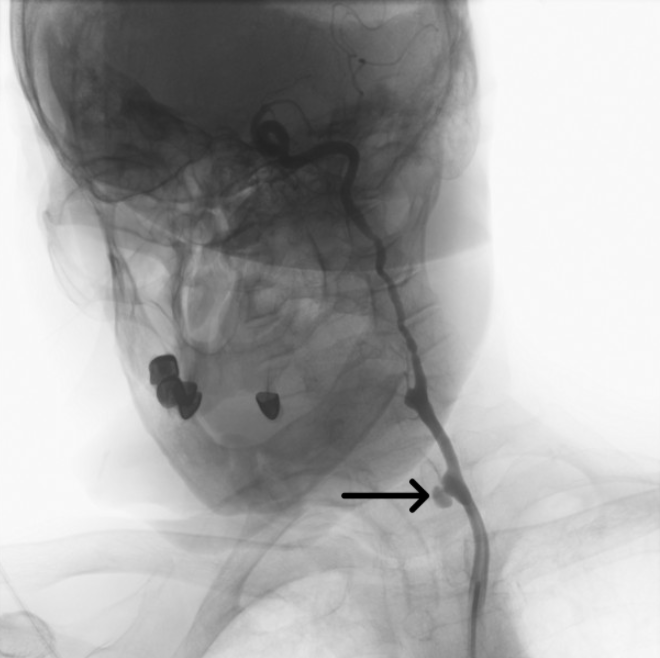

The bleeding segment was selectively wired. A 5 × 40-mm covered stent graft was deployed across the ruptured segment (Figure 2, Video 2); initial deployment was complicated by proximal slippage but hemostasis was ultimately achieved. The stent was then post-dilated with a 7 × 20-mm balloon to optimize apposition (Figure 3, Video 3). Final angiography confirmed complete sealing of the rupture and restoration of antegrade carotid flow (Figure 4, Videos 4 and 5).